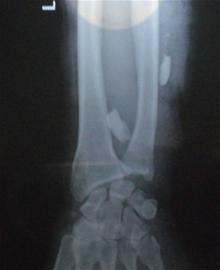

記者趕到401醫(yī)院時,醫(yī)生正在為受傷老人做檢查。記者發(fā)現(xiàn)老人左前臂纏上了厚厚的紗布,而且手腕處的傷口鮮血還不斷往外滲,醫(yī)生用繃帶將傷臂吊在脖子上。老人的右胳膊也有傷口,手腕處纏了厚厚的繃帶。此外,老人的雙手多處劃傷,滿是暗紅色的血漬。醫(yī)生在檢查的過程中,老人家屬向醫(yī)生出示了在當(dāng)?shù)蒯t(yī)院拍攝的X光片,通過X光片可以清晰地看到插入胳膊中的兩顆豬牙。醫(yī)護(hù)人員診斷后將老人送到手術(shù)室準(zhǔn)備手術(shù)。